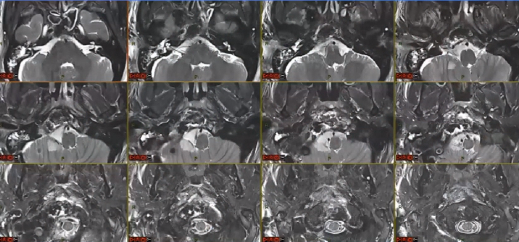

▼这个病例,它影响了颈1颈2.然后没有侵袭到硬膜内,我就不考虑用内镜了。考虑到脑脊液的释放等问题,这里我用了后外侧的一个入路。利用45度的内镜往上看,往上磨除岩骨的后方,可以一直暴露颈内动脉的岩骨段,然后海绵窦段。然后在显微镜下我们可以进行双手的操作,神经外科医生就比较熟悉的了。我们在做手术切除肿瘤切完了之后,还要进行固定。